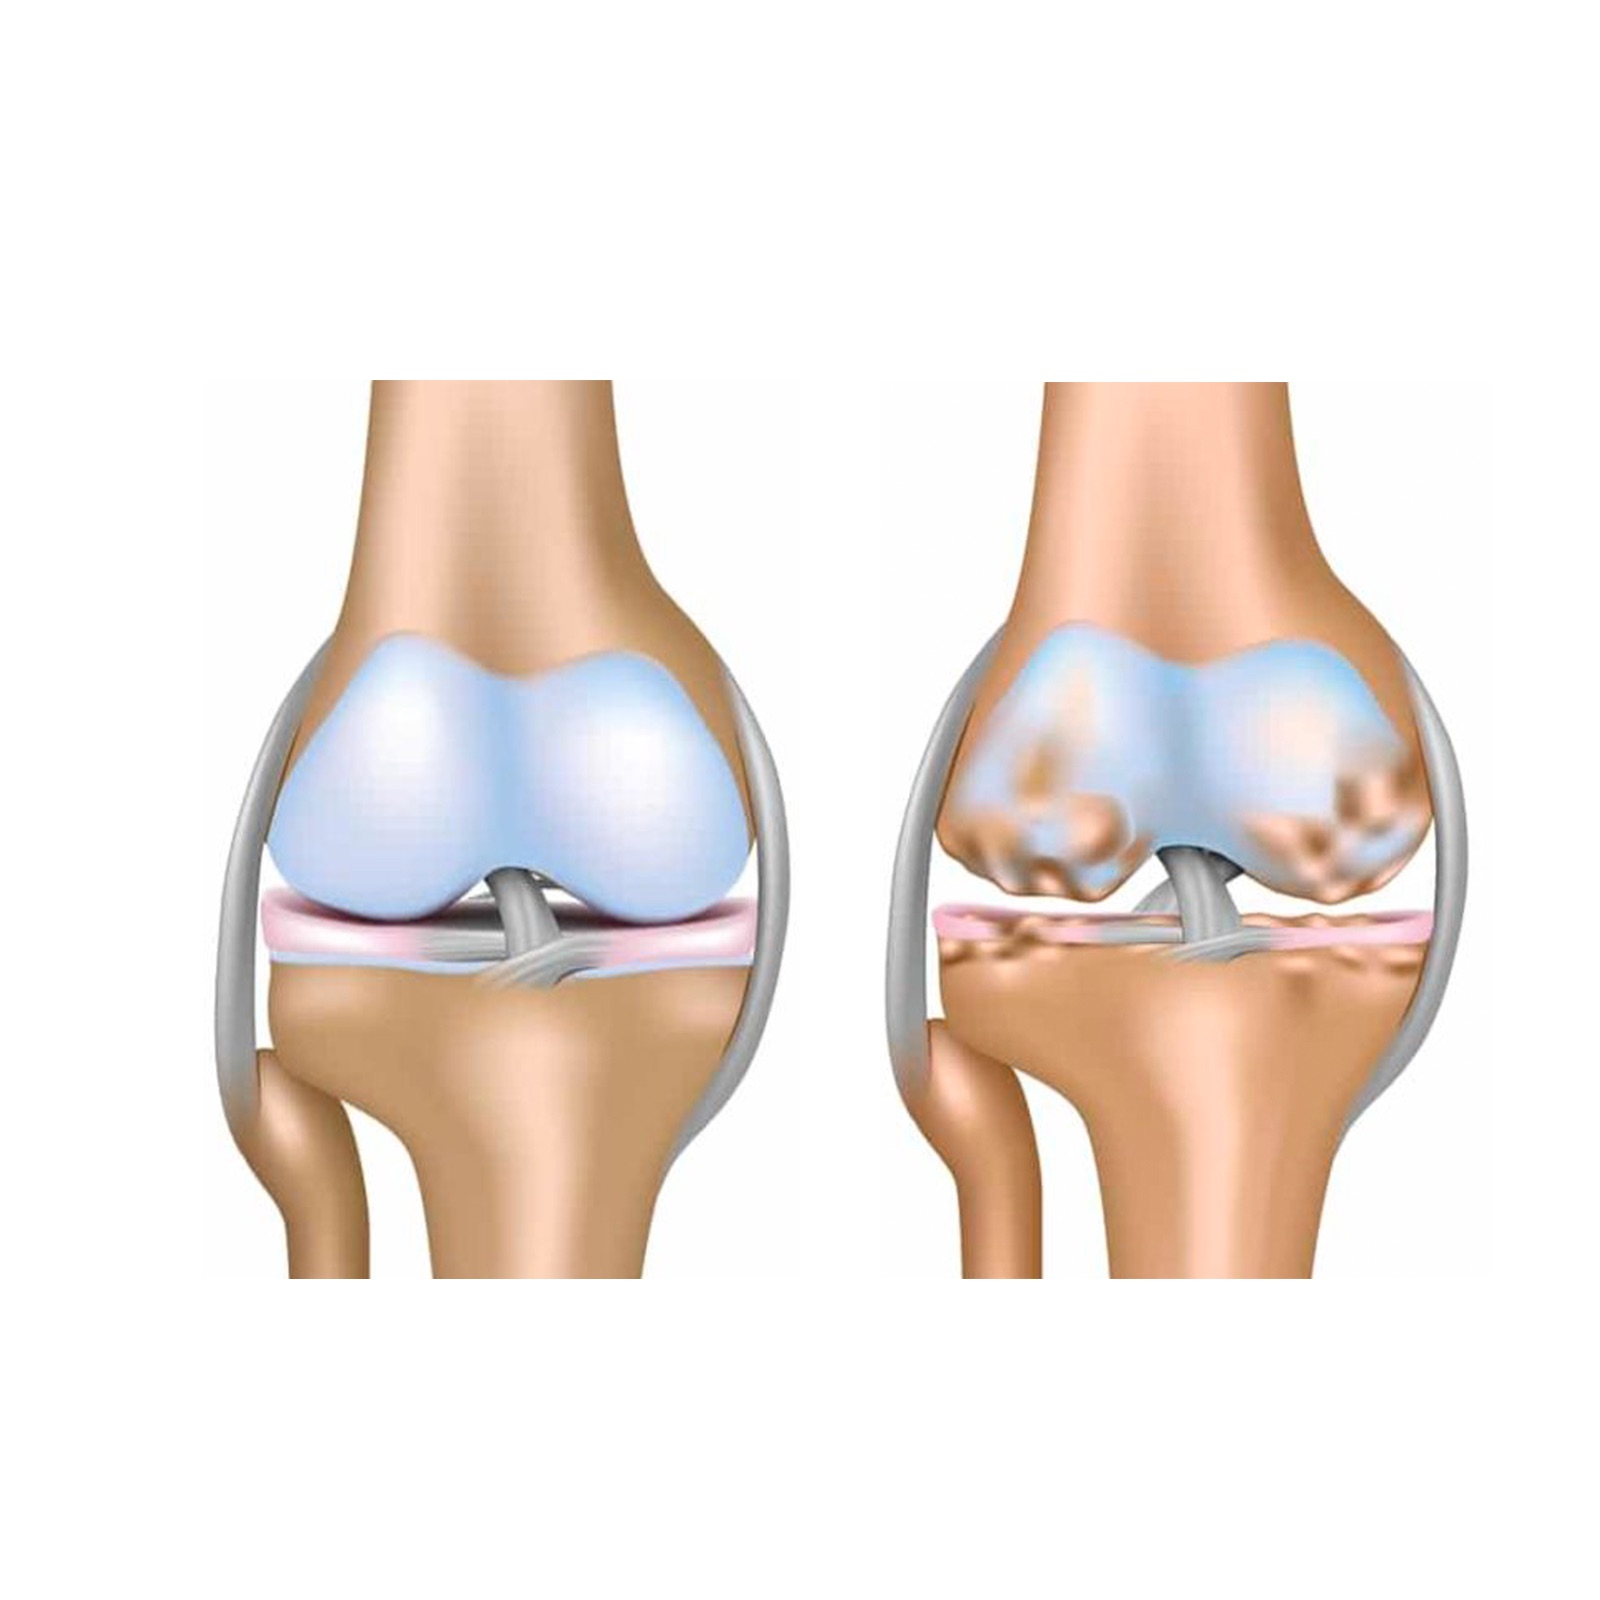

Медицинские снимки: рентген коленного сустава при остеопорозе